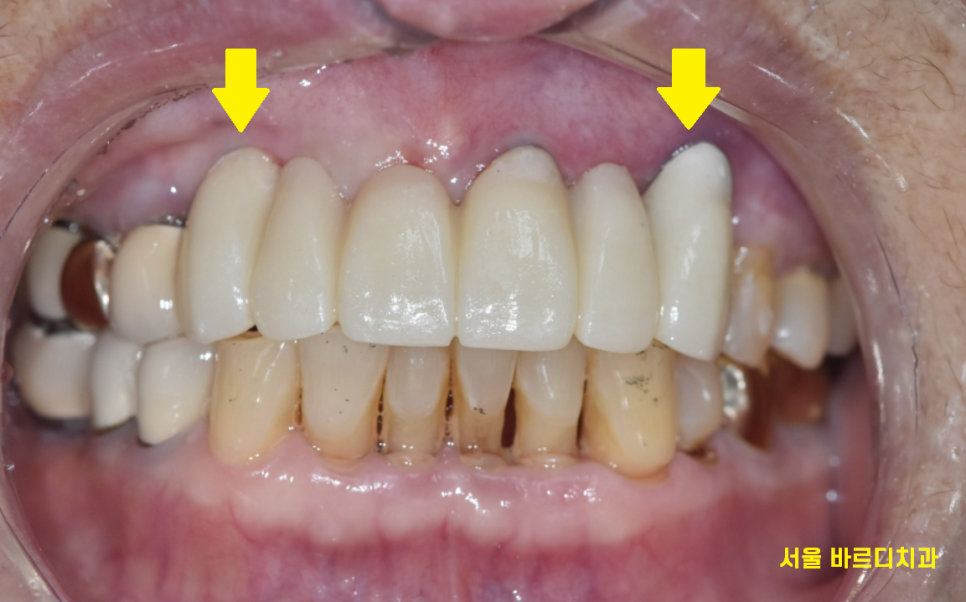

앞니는 노출이 많이 되기에

주변 치아와 자연스럽게 어우러져야하는데요.

티가 나지 않게

자연스러운 미소를 만들어드리는 서울바르디치과입니다.